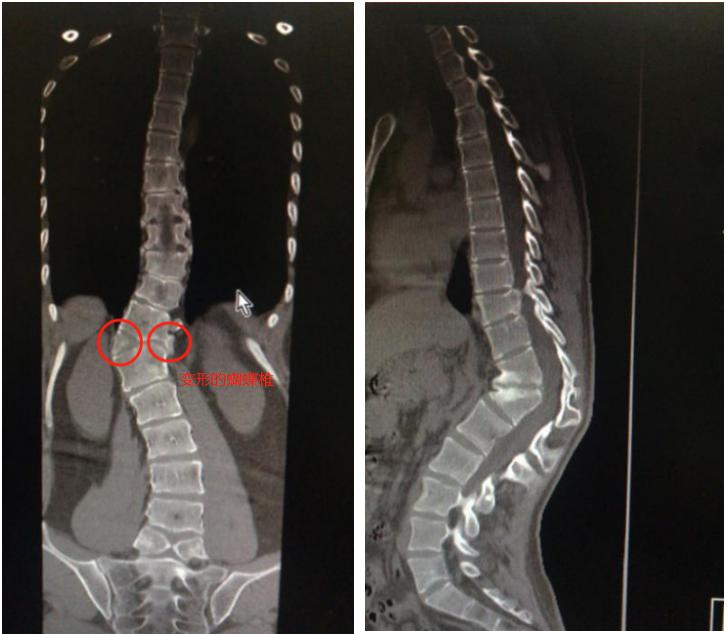

图1术前站立位全脊柱正侧位治疗:后路t4经椎弓根不对称楔形截骨 内

x片c形臂下矫形前后术中及手术前后影像对比:后路胸腰椎截骨矫形术

小李的情况属于前侧和中部椎体形成障碍所致蝴蝶椎,这类畸形病情进展